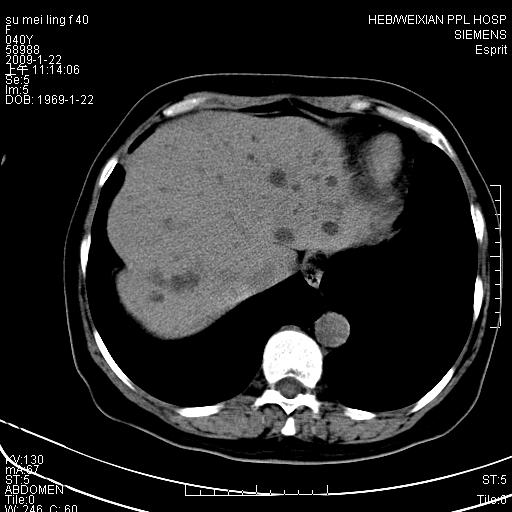

主因食欲不振检查。b超检查肝内片状低密度影。

图象的序列乱,病史也简单,单看这几幅图片考虑——肝囊肿?转移瘤?建议强化

以肝多发性囊肿可能大

我个人认为转移瘤可能性大!建议增强!

考虑多发肝小囊肿,建议增强,不排除囊性转移可能。

多发肝囊肿或caroli

肝内多发囊性低密度灶,以肝囊肿可能性大;建议必要时行进一步检查。

囊性病变沿胆管走向,首先考虑肝内胆管囊肿(caroli)、多发肝囊肿不除外